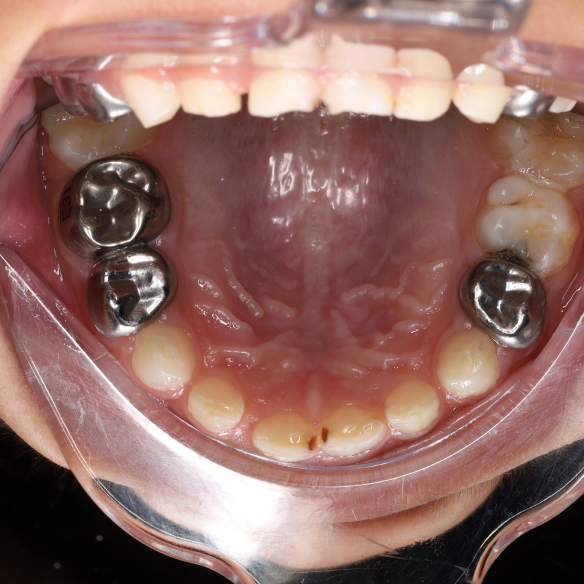

SSC (Stainless Steel Crown) là mão răng bằng thép không gỉ, được thiết kế sẵn với nhiều kích cỡ khác nhau, thường dùng để phục hồi răng sữa đã bị sâu lớn hoặc tổn thương nặng. Đây là một dạng phục hình toàn phần bao phủ toàn bộ thân răng, giúp bảo tồn và duy trì chức năng của răng sữa cho đến khi thay răng vĩnh viễn.

Mão SSC giúp bao phủ toàn bộ thân răng, giảm nguy cơ nứt vỡ và tái nhiễm khuẩn.